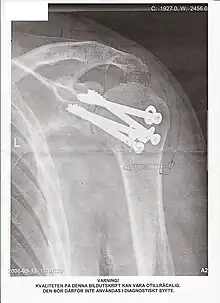

Arthrodèse

Une arthrodèse est une intervention chirurgicale destinée à bloquer une articulation lésée par l'obtention d'une fusion osseuse (en général de l'extrémité des os) dans le but de corriger une déformation ou d'obtenir l'indolence. C'est souvent une opération non réversible. L'opération inverse, qui consiste à désolidariser des os fusionnés, s'appelle une désarthrodèse.